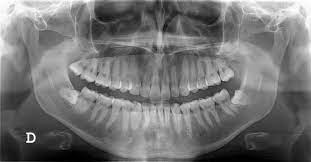

Educación del paciente: Las radiografías dentales son una herramienta educativa poderosa. Al mostrar las imágenes a los pacientes, pueden comprender mejor los problemas dentales que tienen y la importancia de los tratamientos recomendados. Como asistente dental, pueden desempeñar un papel importante al explicar las radiografías a los pacientes y responder a sus preguntas.